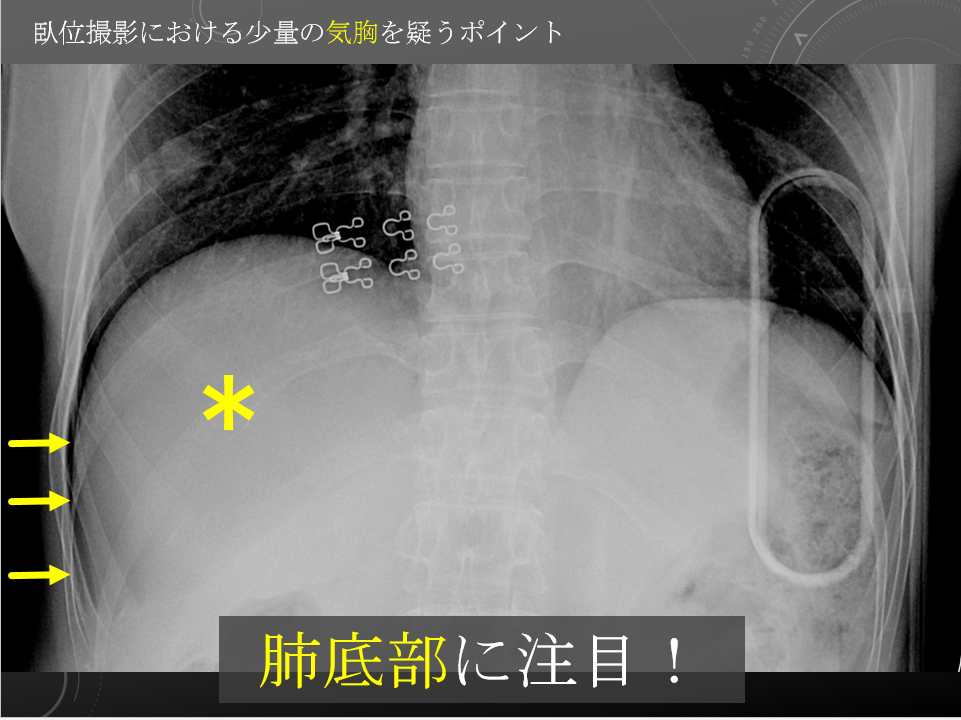

胸部臥位単純写真

比較画像はありません。

気管挿管後です。右片肺挿管に近い状況です。

右気胸が認められます。

左肺野および心縦隔陰影に異常所見は明らかではありません。

大量胸水貯留所見は認められません。

同日 CT で認められている右鎖骨遠位部および、第4-7肋骨骨折が確認されます。第11胸椎骨折は、本検査上指摘困難です。

右気胸、右多発肋骨骨折、右鎖骨骨折。

気管挿管後:右片肺挿管に近い状況です。

胸部臥位単純写真

比較画像はありません。

気管挿管後です。右片肺挿管に近い状況です。

右気胸が認められます。

左肺野および心縦隔陰影に異常所見は明らかではありません。

大量胸水貯留所見は認められません。

同日 CT で認められている右鎖骨遠位部および、第4-7肋骨骨折が確認されます。第11胸椎骨折は、本検査上指摘困難です。

右気胸、右多発肋骨骨折、右鎖骨骨折。

気管挿管後:右片肺挿管に近い状況です。